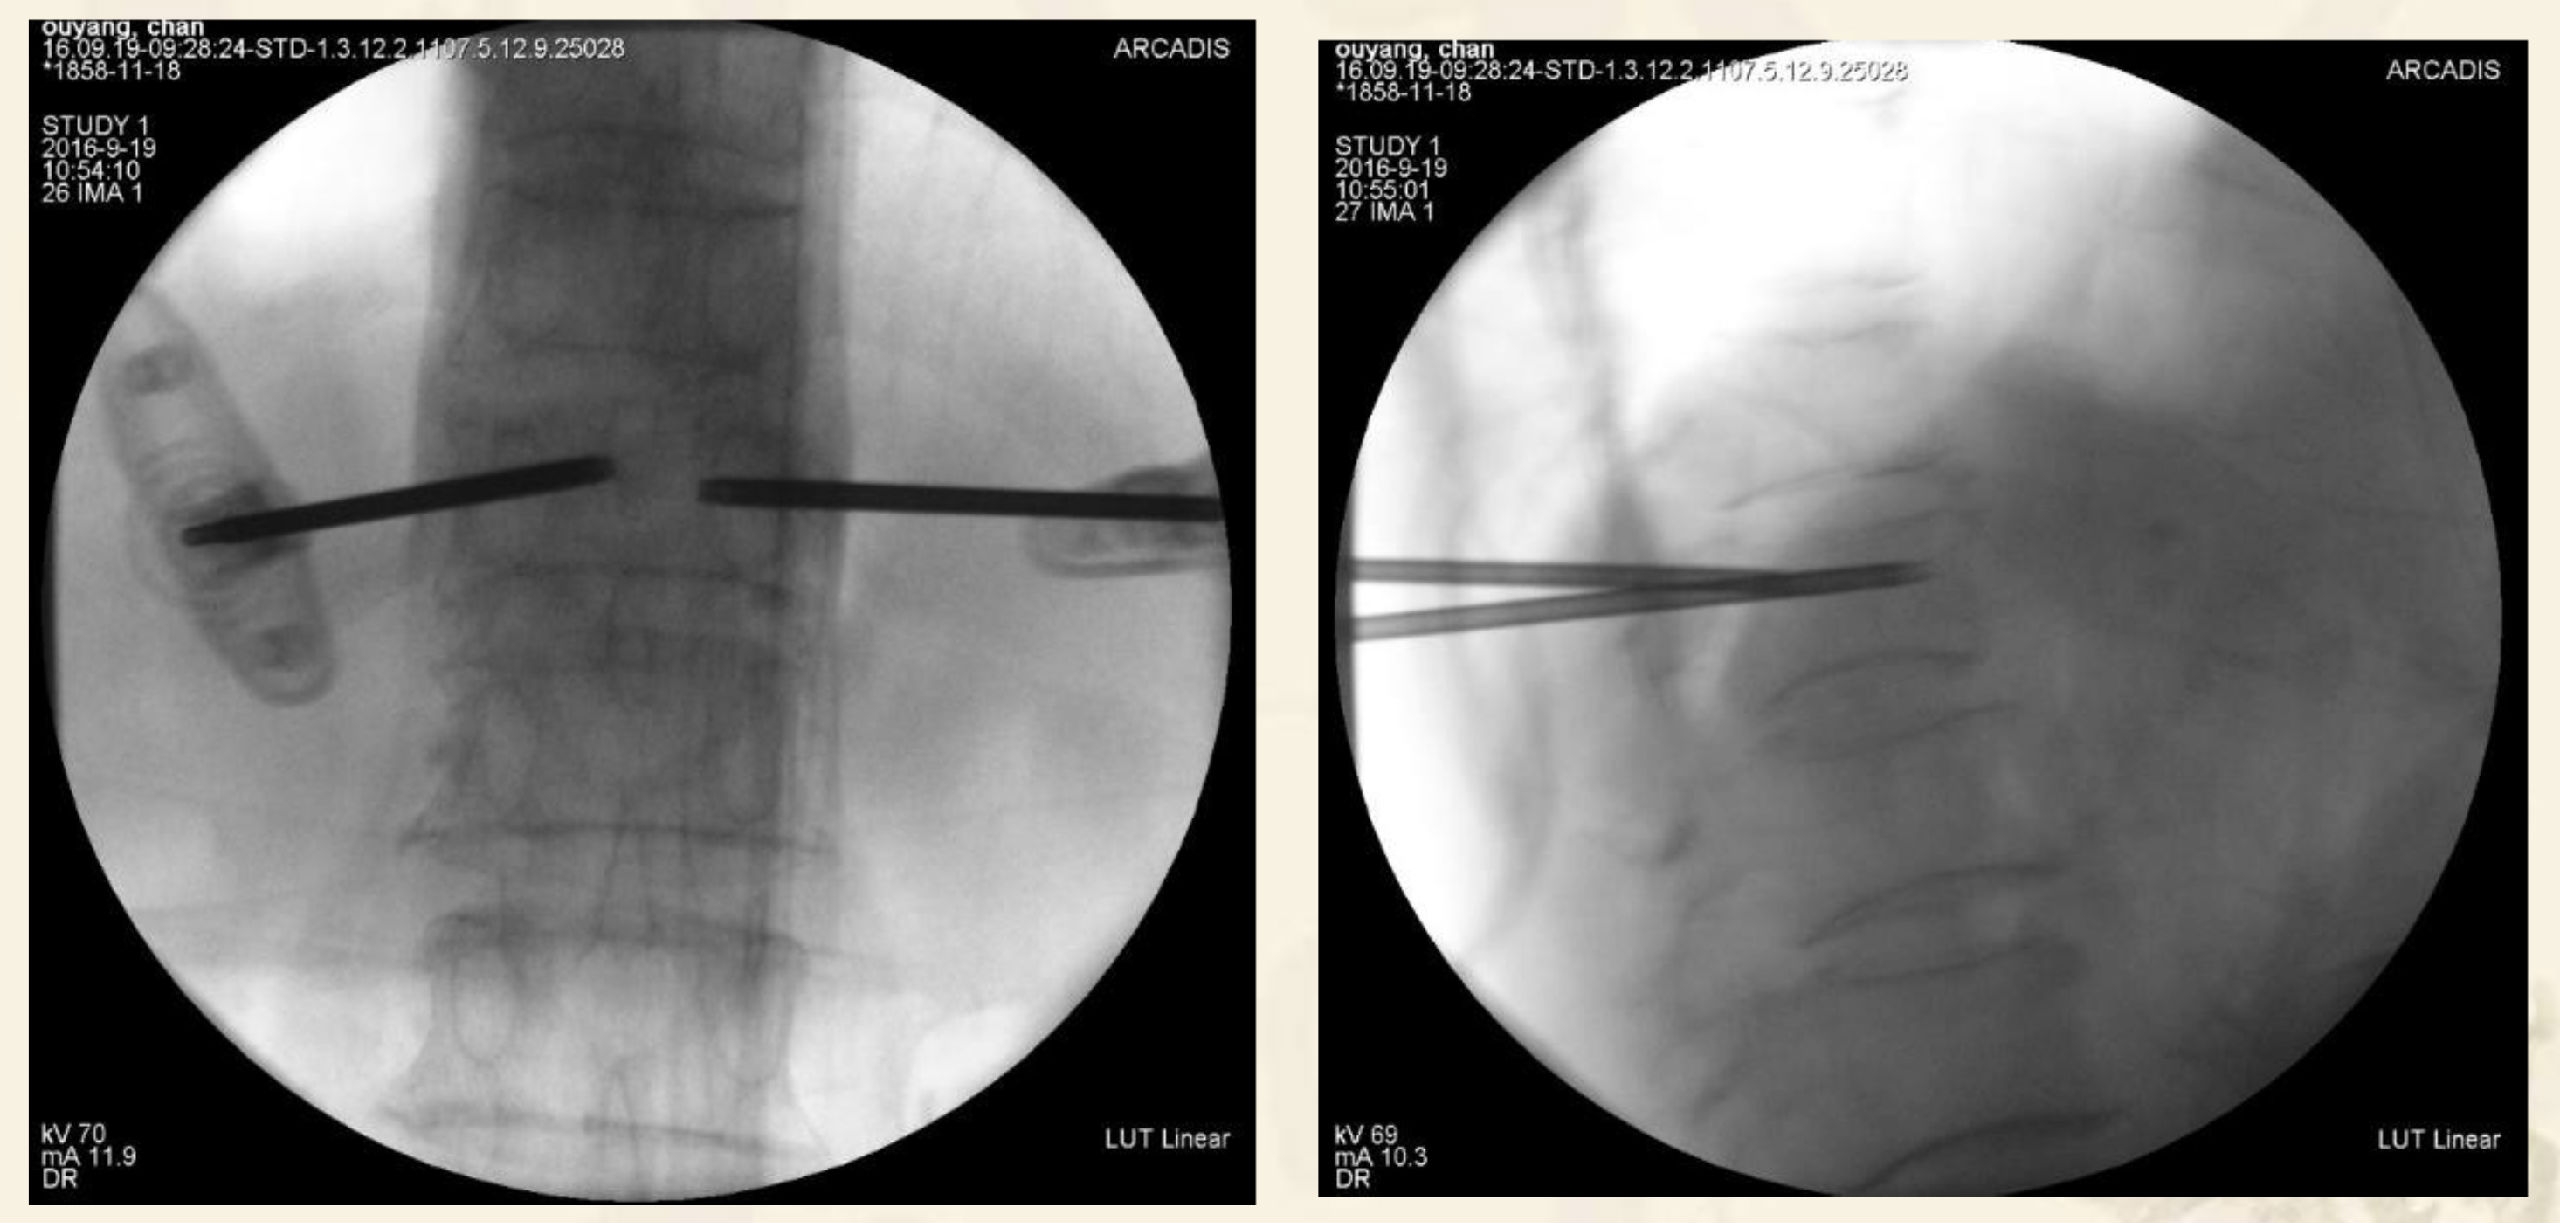

术中透视图

透视引导下,经椎弓根入路或根旁

靶向骨折区置管

侧开口推杆控制骨水泥弥散方向